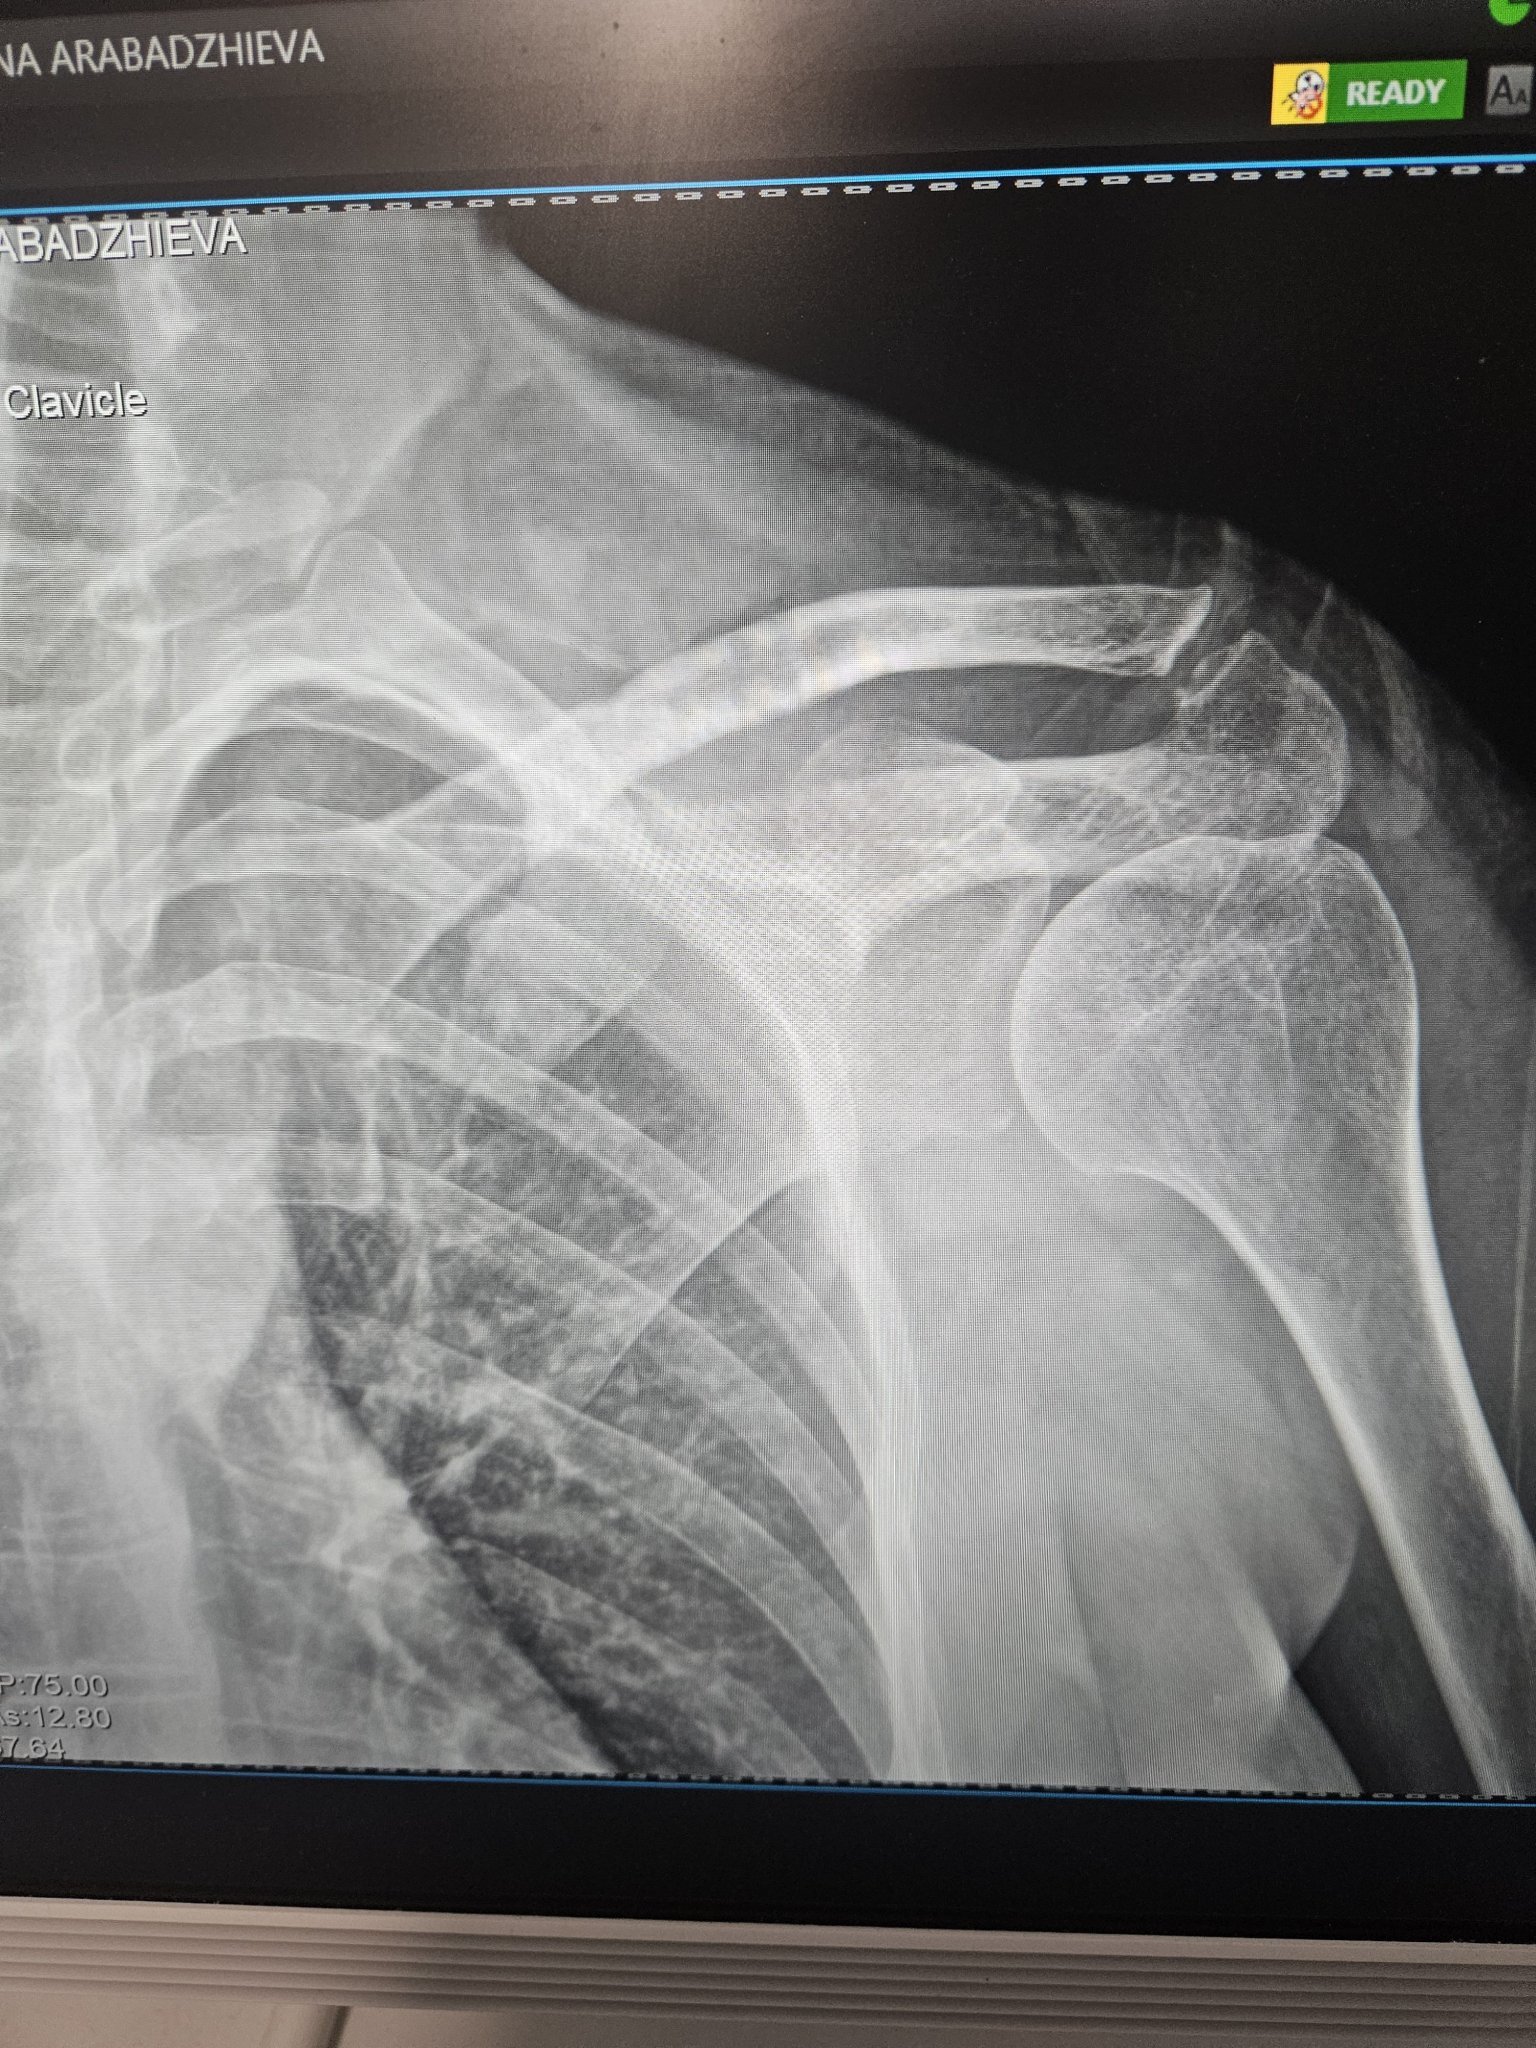

Какво е препоръчителното лечение за частична руптура на сухожилието на m.supraspinatus при раменна травма?

Направете рентгенова снимка на ходилото фас и профил (ако кривата кост е на ходилото).